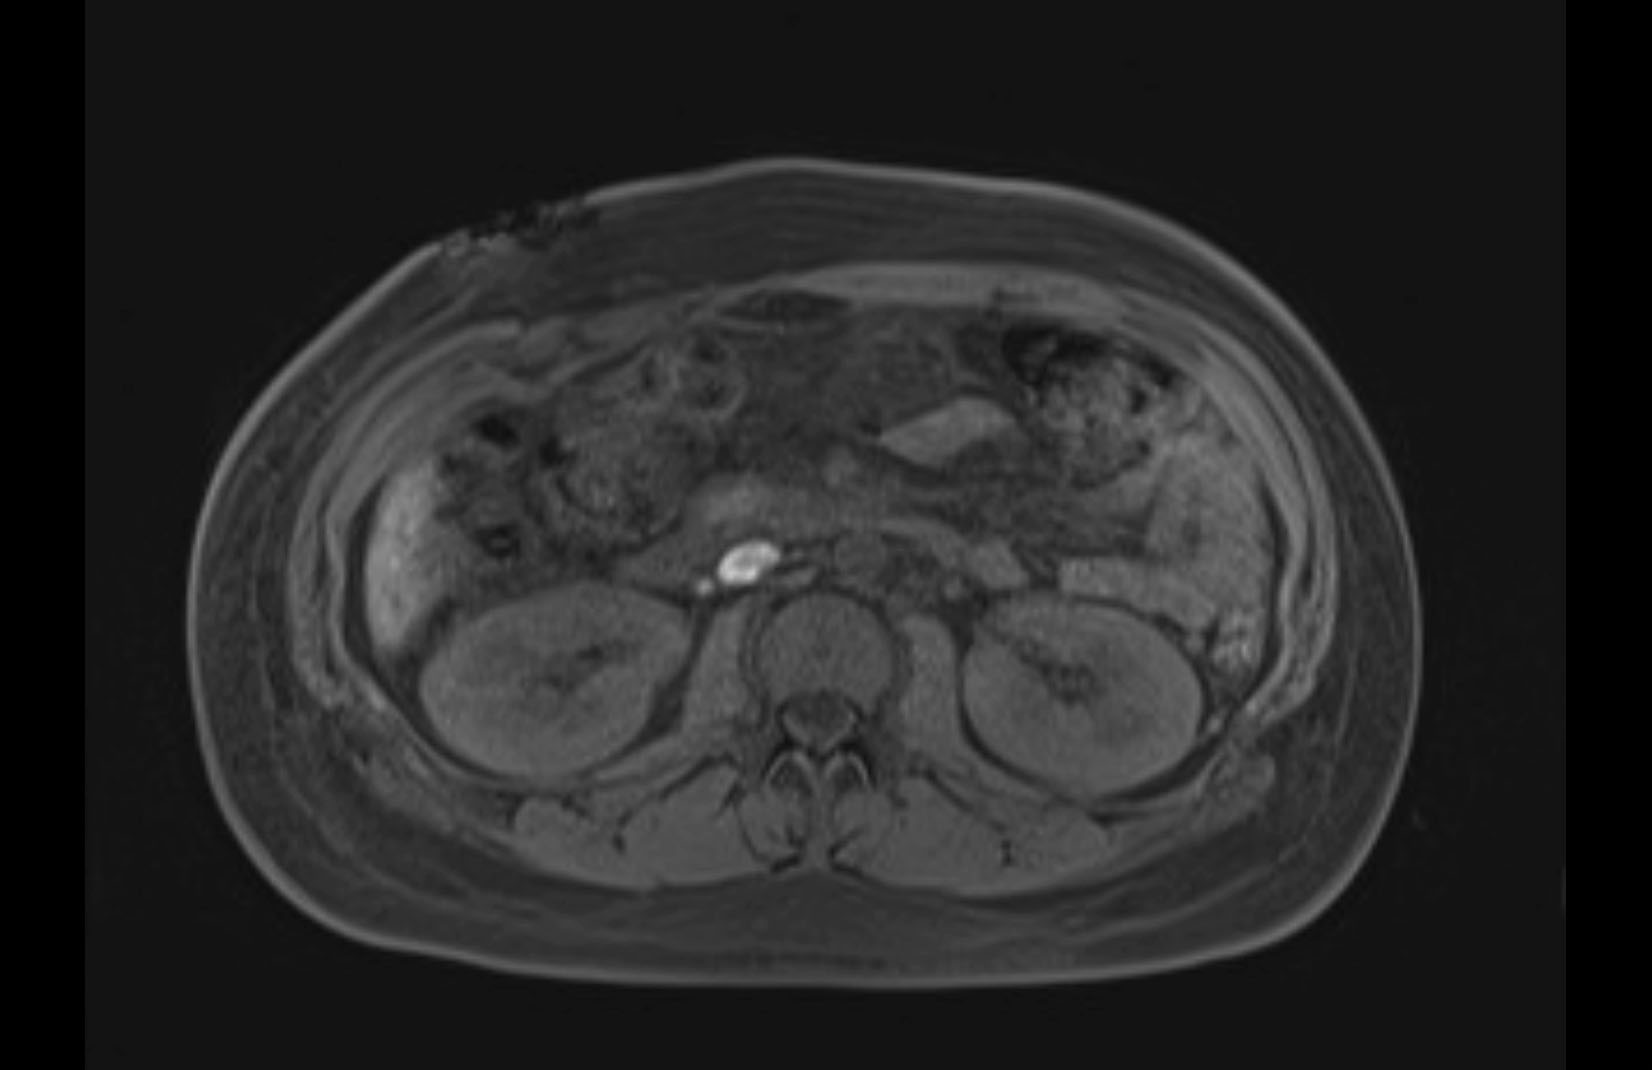

MRI T1

MRI T2

Imaging analysis

Based on initial findings, which issue(s) would you be most concerned about?